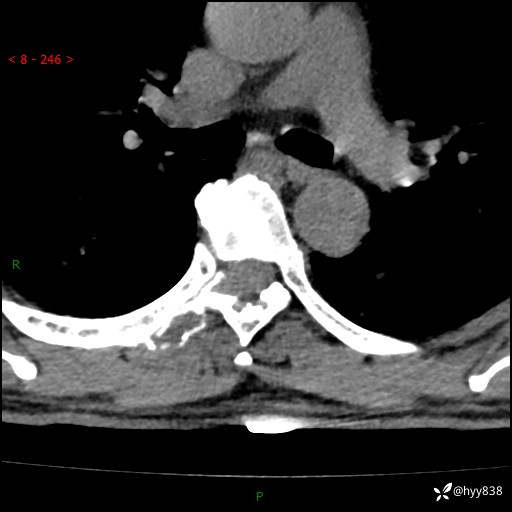

胸椎CT平扫(骨窗+软组织窗)